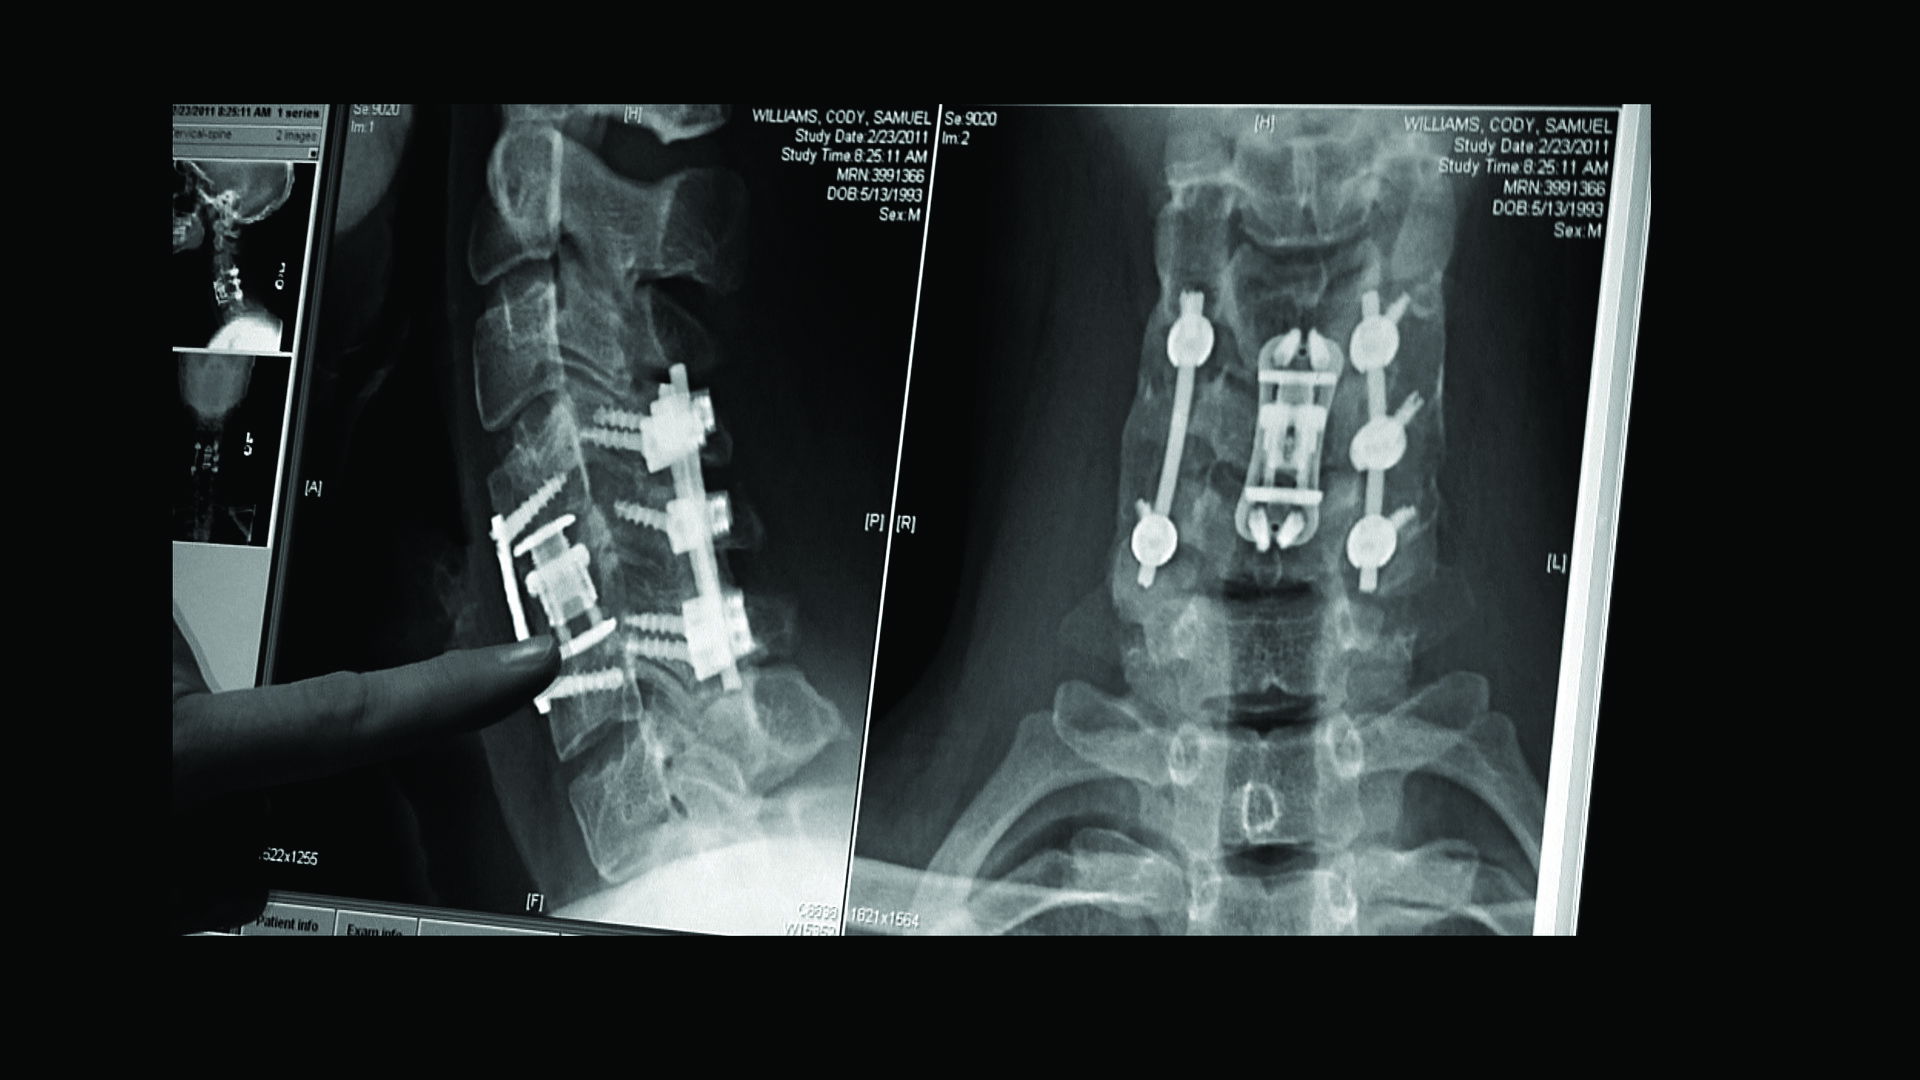

Cody Williams